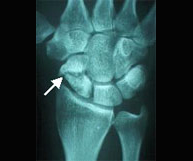

La articulación de la muñeca une las regiones del antebrazo y la mano implicando la porción inferior del cúbito y radio así como los huesos del carpo.Las fracturas del radio distal son las más frecuentes de la extremidad superior. En gente joven se asocian a traumatismos de alta energía como accidentes de tráfico, caídas desde altura o accidentes deportivos. En el anciano lacarencia de hueso a este nivel (osteoporosis) hace de esta región un lugar muy susceptible de fractura con pequeños impactos.

El paciente de edad se beneficia habitualmente del tratamiento conservador con escayola. En el paciente joven el desplazamiento suele ser difícilmente manejable con inmovilización con yeso por lo que es frecuente la realización de una pequeñaintervención para la recuperación anatómica de la muñeca pudiendo reincorporarse a su actividad habitual en el menor tiempo posible y con el menor riesgo de complicaciones.Dentro de la región anatómica de la muñeca se encuentran los huesos del carpo. El hueso escafoides es el que se fractura con más frecuencia tras caídas sobrela mano en extensión. Es por ello una lesión característica en deportes como motociclismo, ciclismo y patín donde se pueden sufrir traumatismos a gran velocidad. El dolor se localiza siguiendo el eje del pulgar pero a nivel de la muñeca y el dolor a la palpación en esta zona (tabaquera anatómica) es extremo. Las fracturas desplazadas se suelen estabilizar quirúrgicamente sin cicatriz,a través de la introducción percutánea de un tornillo intraóseo que permite el inicio de la movilización de la articulación inmediatamente.